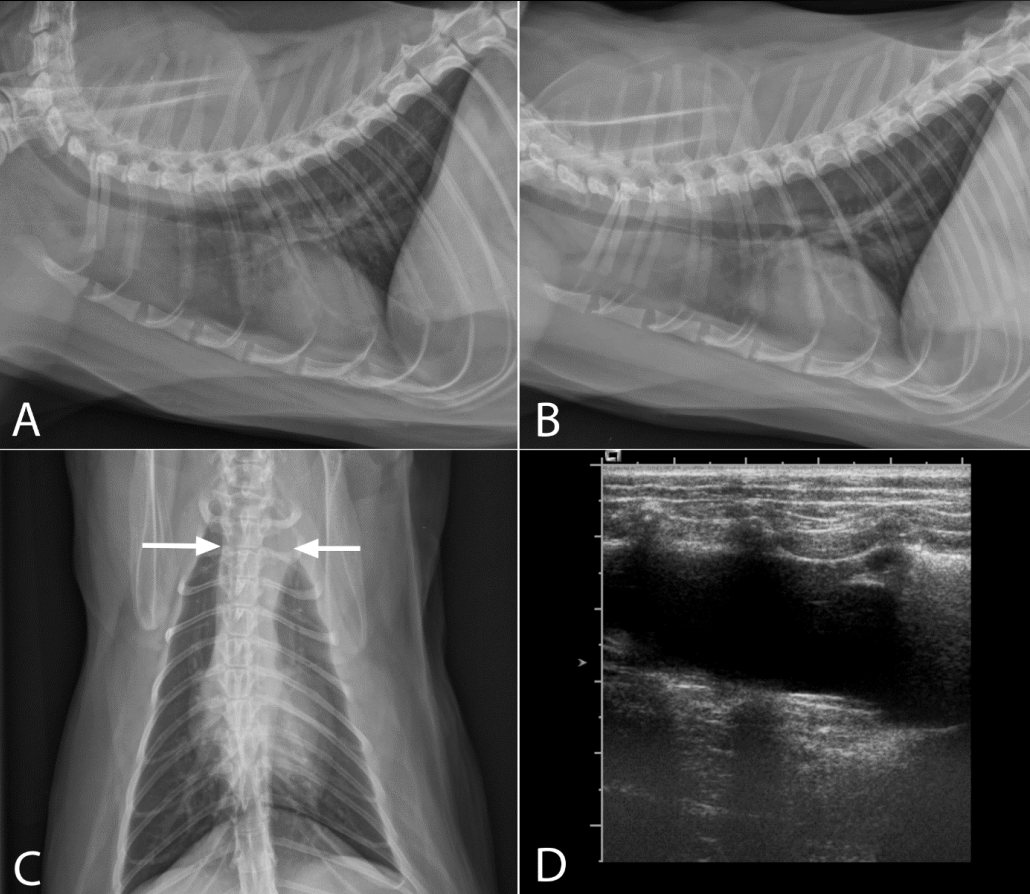

What is shown in this image?

What is shown in these images?

A

sternal lymphadenopathy

tracheobronchial lymphadenopathy

-widening on mainstem bronchi

generalized lymphadenopathy:

-widening of mediastinum

-deviation of mainstem bronchi